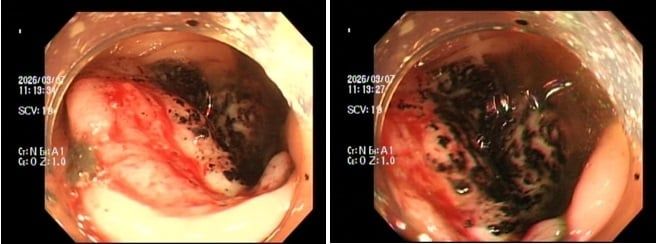

- Trường hợp 1: Chị P.V.P.U (sinh năm 1991) đến khám chỉ vì... ông xã thấy dạo này da dẻ chị quá xanh xao. Bản thân chị thỉnh thoảng cũng cảm thấy đau bụng nhẹ, thoáng qua nhưng lại tặc lưỡi bỏ qua vì nghĩ là rối loạn tiêu hóa thông thường. Khi thăm khám, bác sĩ phát hiện chị bị thiếu máu nặng. Ngay lập tức, chị được chỉ định nội soi đại tràng, kết quả khiến cả hai vợ chồng sững sờ: Có một khối u lớn ở đại tràng phải, bề mặt loét và rất dễ chảy máu, kết quả mô học khẳng định: Ung thư đại trực tràng.

- Trường hợp 2: Anh N.H.H.H (sinh năm 1995) đến viện với dáng vẻ mệt mỏi rã rời, than phiền hay bị chóng mặt kèm theo rối loạn đi cầu. Cứ nghĩ do làm việc quá sức, nhưng kết quả xét nghiệm lại báo động tình trạng thiếu máu nặng. Bác sĩ cho tiến hành nội soi đại trực tràng và phát hiện một khối u dạng vòng nhẫn đang chảy máu rỉ rả ở vùng trực tràng. Giải phẫu bệnh một lần nữa gọi tên: Ung thư trực tràng.